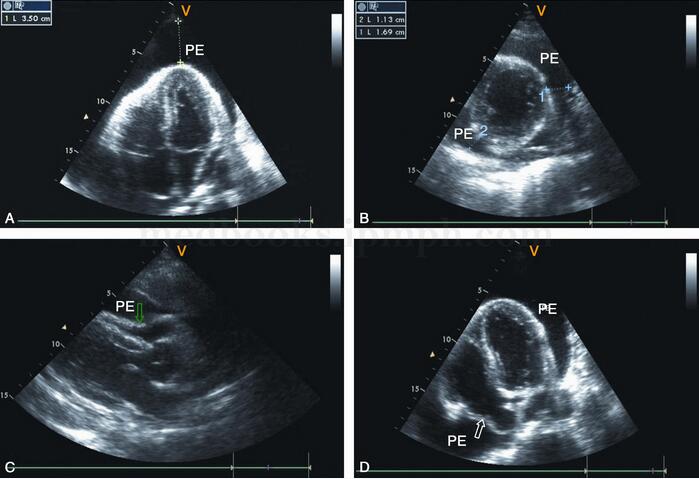

图2‐1‐229 大量心包积液,肝静脉明显扩张